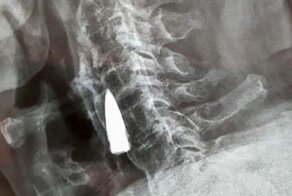

- Мужчина узнал о пуле, засевшей в его теле, 77 лет спустя